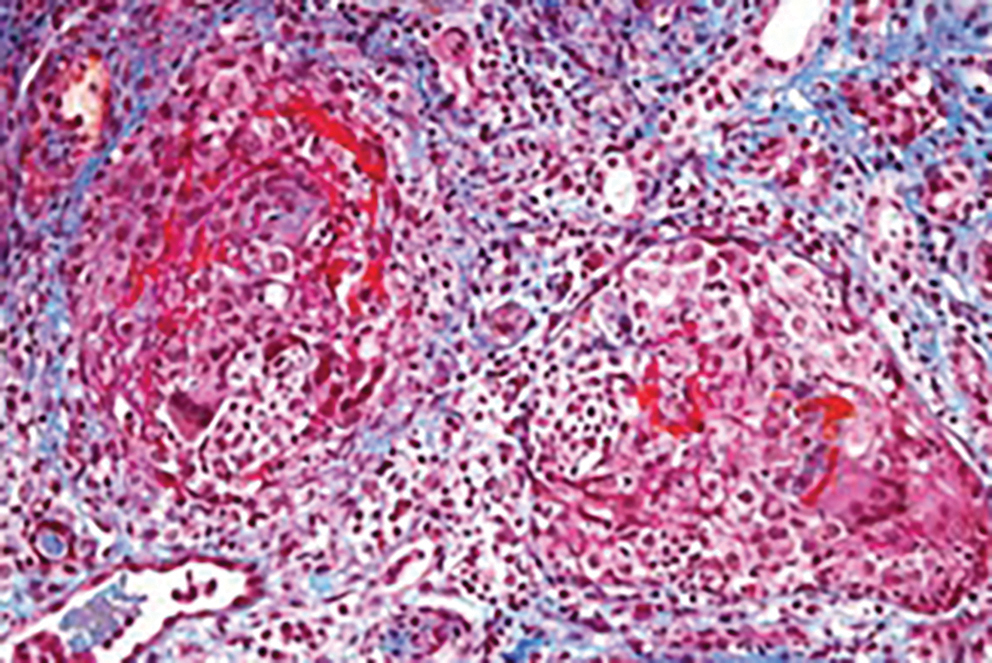

Pro výraznou anémii jsme pacientce vstupně podali transfuzi erytrocytů. Při nálezu vysokých hodnot zánětlivých parametrů a trvání febrilií jsme pokračovali v parenterální antibiotické léčbě. V rámci diferenciální diagnostiky možné infekční příčiny obtíží byla doplněna široká mikrobiologická vyšetření s negativním nálezem: výtěr z nazofaryngu na polymerázovou řetězovou reakci (PCR) respiračních virů, výtěr z krku, z rekta, PCR ze stolice, hemokultivace, PCR virů z plné krve – virus Epsteina–Barrové (EBV), cytomegalovirus (CMV), virus herpes simplex (HSV), virus varicella zoster (VZV), lidský humánní herpetický virus (HHV6), HHV7, parvovirus B19, adenovirus, sérologie Toxoplasma gondii, sérologie Chlamydophila pneumoniae, Mycoplasma pneumoniae, brucelózy, tularemie, listeriózy, Yersinia enterocolitica, antigen rodů Candida a Aspergillus. Na ultrazvuku břicha byla popsána pouze difuzní parenchymová léze ledvin bez další patologie. Rentgen hrudníku ukázal pouze nevýrazný zánětlivý infiltrát vlevo parahilózně. Bylo doplněno základní imunologické vyšetření (imunoglobuliny, autoprotilátky: antinukleární protilátky [ANA], protilátky proti cytoplazmě neutrofilních leukocytů [ANCA], protilátky proti dvouvláknové DNA [dsDNA], protilátky proti extrahovatelnému nukleárnímu antigenu [ENA], C3 a C4 složka komplementu) – vše v normě. V moči přetrvával nález nefrotické proteinurie smíšeného rázu. Šestý den hospitalizace byla provedena renální biopsie s překvapivým nálezem – anti‑GBM floridní nekrotizující glomerulonefritidy s objemnými epitelovými srpky s rozsáhlým postižením všech glomerulů ve vzorku (obr. 1). V intersticiu byl nález difuzního lymfocytárního infiltrátu s počínající fibroprodukcí. Imunofluorescenční vyšetření odhalilo lineární depozita imunoglobulinu G (IgG) podél glomerulární bazální mebrány (obr. 2), složka C3 byla pozitivní pouze fokálně v cévách. V séru byl následně zjištěn vysoký titr anti‑GBM protilátek 18887 CU. Pacientce byl zaveden akutní hemodialyzační katétr a byla zahájena agresivní imunosupresivní léčba rychle progredující glomerulonefritidy.

V rámci diagnostiky GN pátráme po přítomnosti anti‑GBM protilátek v séru či v bioptickém vzorku ledviny. Zvýšený titr sérových anti‑GBM protilátek zjišťujeme u 90 % pacientů. V renální biopsii typicky nacházíme RPGN a přítomnost IgG podél glomerulárních kapilár, někdy též podél distálních tubulů. Vzácně může být namísto IgG zjištěna pozitivita IgA či IgM.